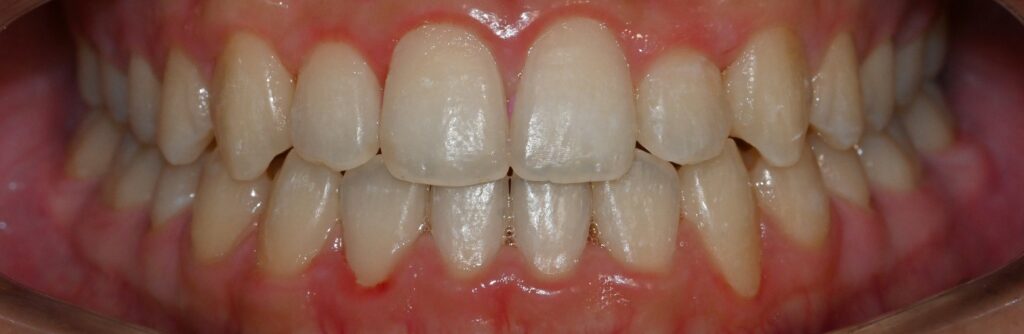

성공적인 치료 결과와 향후 관리

치료 완료 후 반대교합이 완전히 해소되면서 안정적으로 맞물리는 교합을 달성할 수 있게됩니다. 이는 단순히 치아 배열의 개선을 넘어 전체적인 구강 기능의 향상을 의미합니다. 정상적인 교합 관계가 회복되면서 저작 기능이 개선되며 심미적으로도 자연스러운 미소를 만들 수 있습니다.

특히 주목할 점은 골격적 한계가 있는 상황에서도 적절한 치료 계획과 정밀한 실행을 통해 만족스러운 결과를 얻을 수 있다는 사실입니다.